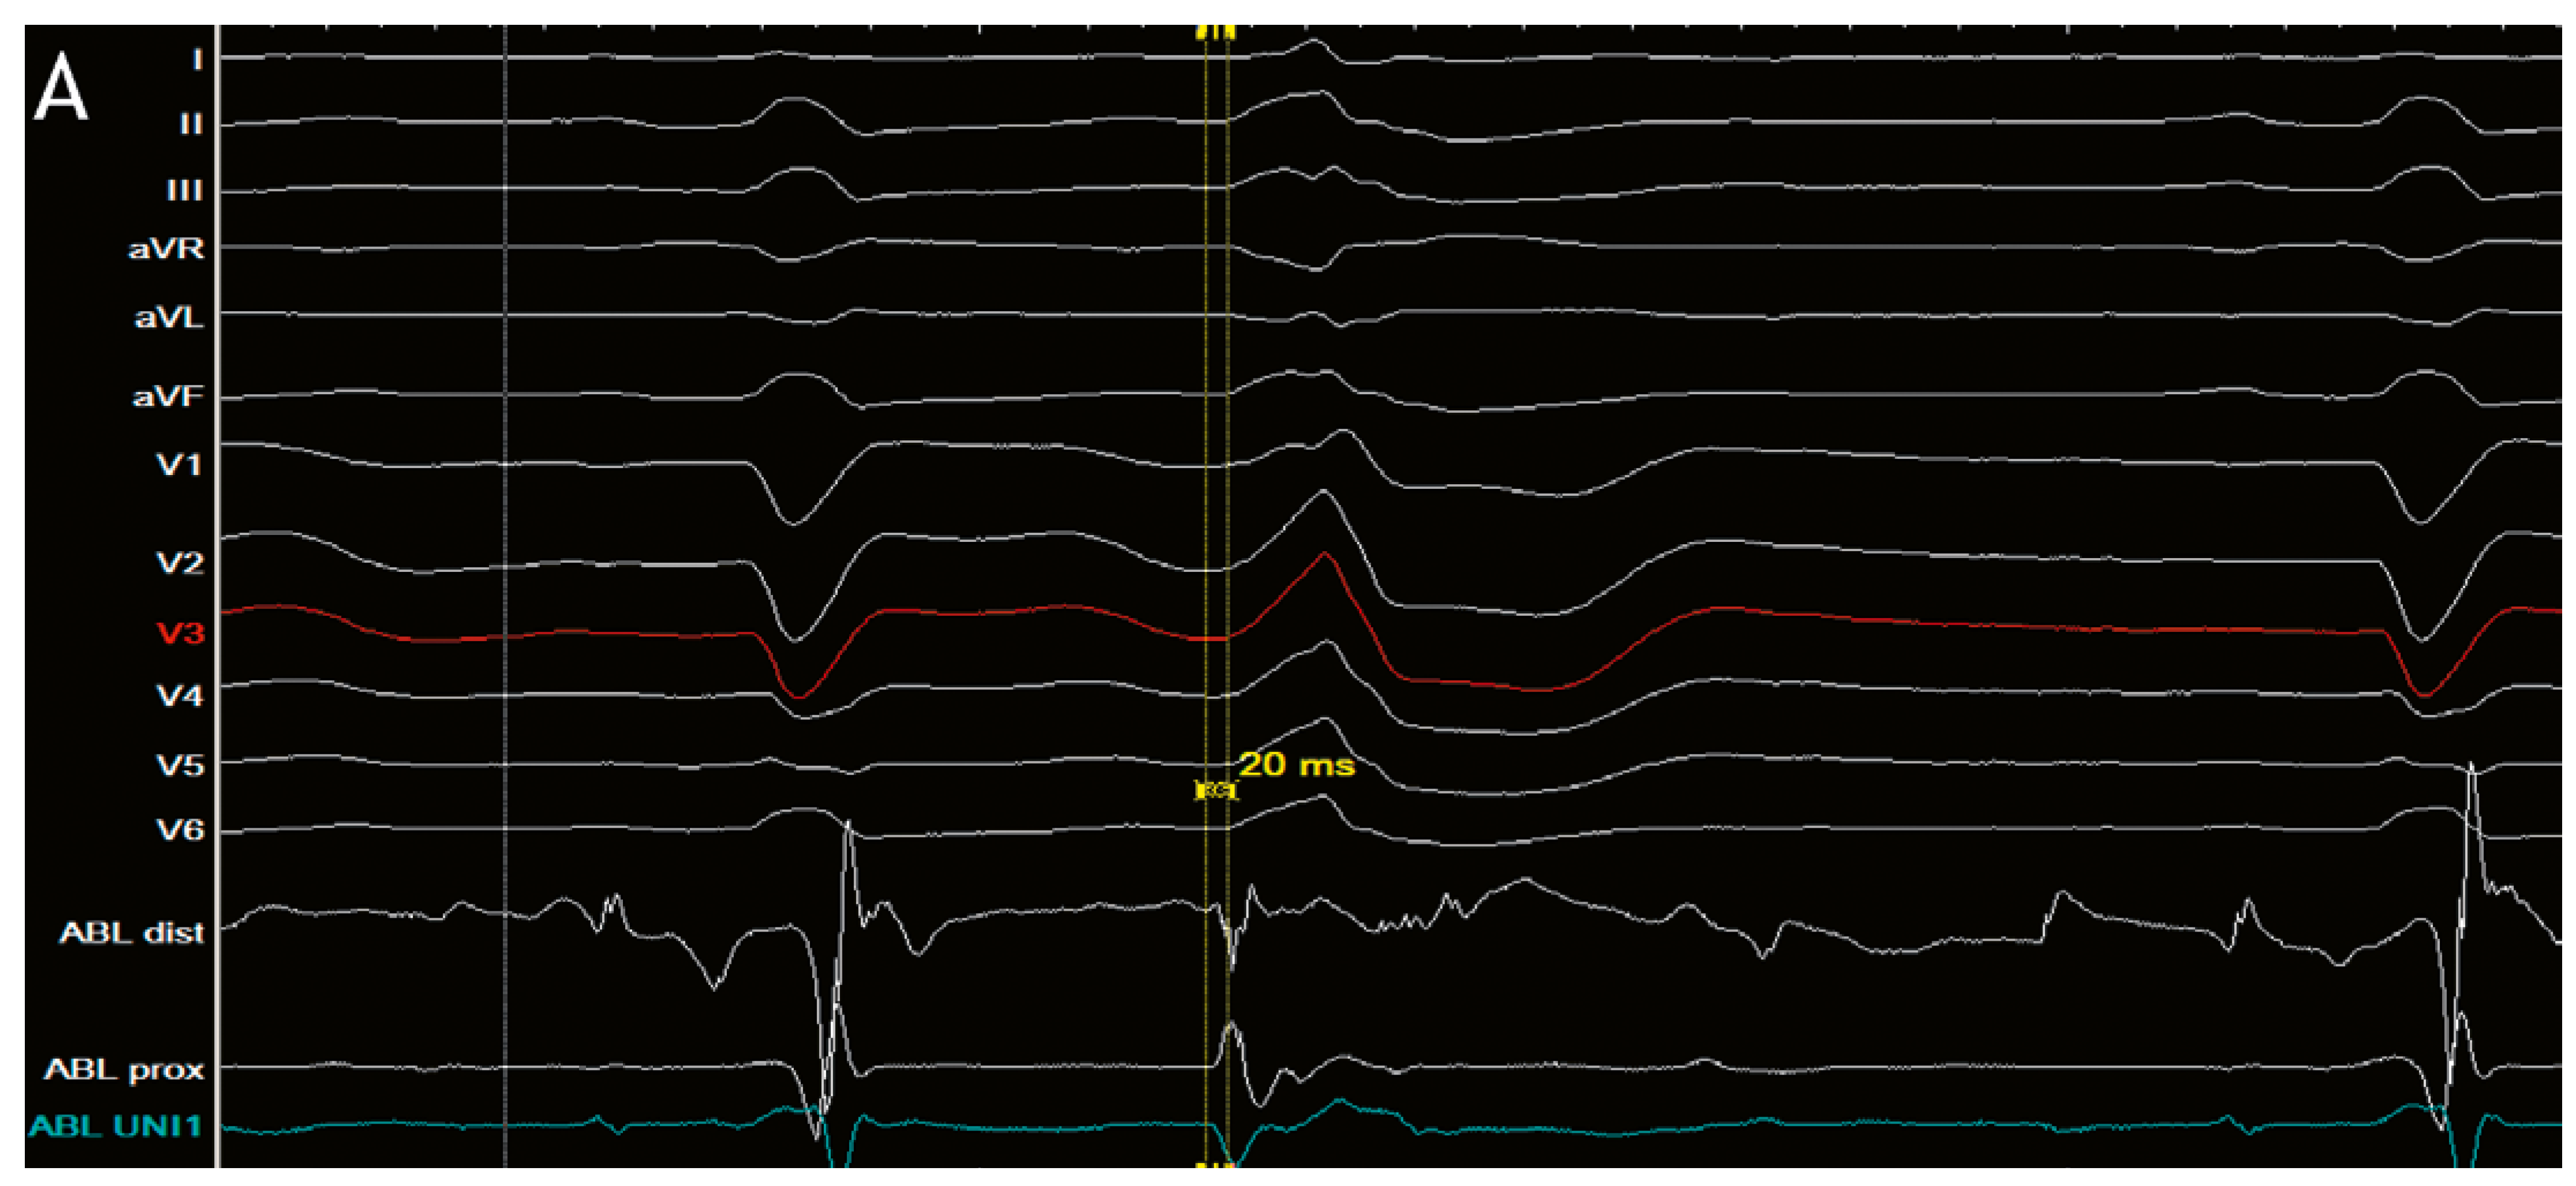

Clinical case